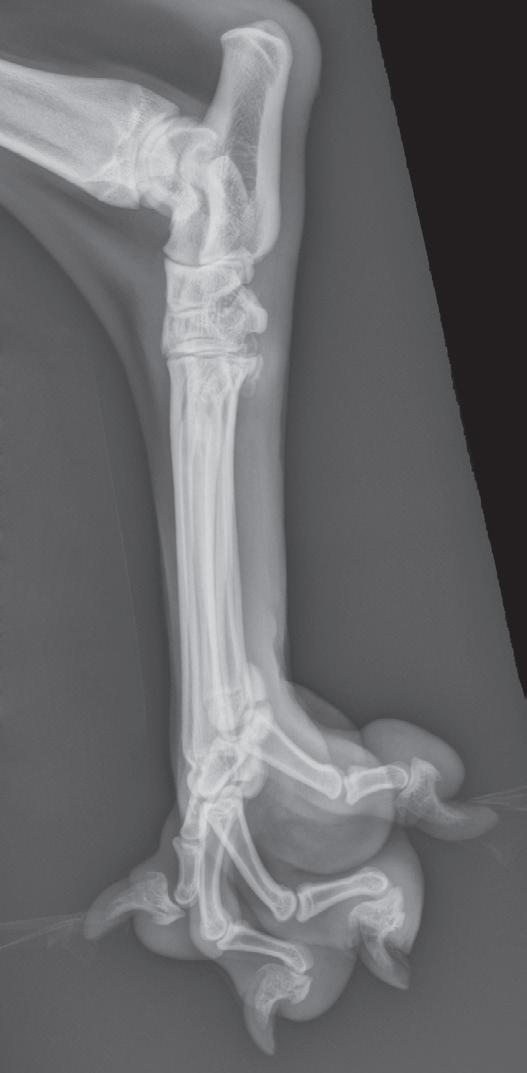

Figure 1-4. Correct orientation of lateral views of two extremities. A lateral view of a humerus (A) and a lateral view of a tarsus/pes (B) are shown here. Note the difference in directional terms depending on whether the part being imaged is above or below the tarsocrural or antebrachiocarpal joint.